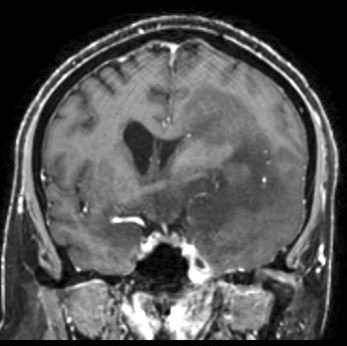

Radiology description

- CT:

- Expanding, intra-axial, poorly defined mass of low density

- Variable calcification may be seen

- Contrast enhancement and central hypodensity due to necrosis, occur with higher grades

- MRI:

- T1 hypodensity and T2 hyperintensity

- T2 hyperintensity with relative FLAIR sequence hypointensity (T2 FLAIR mismatch) is a relatively suggestive indication of IDH mutant astrocytoma (Clin Cancer Res 2017;23:6078)

- Distortion and enlargement of involved areas, including associated cortical ribbon

- Contrast enhancement is typically present in higher grade tumors (J Neurooncol 2019;141:327)

- Ring-like enhancement around central necrosis typical of grade 4

Radiology images